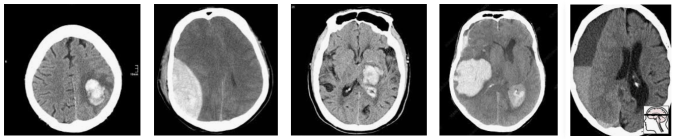

In this population, we have a pretty reasonable “clinical” mix of cases. 3 intra-cerebral bleeds (likely related to high blood pressure or stroke), and two traumatic bleeds (a subdural on the right, and an extradural second from the left).

Now let’s sample this population to build our test set:

Randomly, we end up with mostly extra-axial (outside of the brain itself) bleeds. A model that performs well on this test will not necessarily work as well on real patients. In fact, you might expect a model that is really good at extra-axial bleeds at the expense of intra-cerebral bleeds to win.